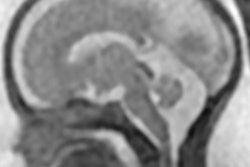

(a) Axial, (b) sagittal, and (c) coronal fetal T2-weighted MR images were obtained in a 29-year-old woman with confirmed Zika virus infection, initially seen for characteristic rash at 12 weeks of gestational age. (d) Axial postnatal CT image and (e-g) axial and (h) coronal T2-weighted MR images were obtained in her neonate. The fetal MR images obtained at 34 weeks (a-c) show asymmetrical ventriculomegaly with a septation in the right occipital horn (arrowhead on a), small frontal lobes, thinning of the occipital parenchyma (left worse than right), underdeveloped sylvian fissures, and regions of thickened cortex, as in the right frontal lobe, which is suggestive of polymicrogyria (arrow on a). There is abnormal, increased signal intensity in the white matter. The postnatal CT image (d) obtained in the 22-day-old neonate shows punctate calcifications at the gray matter-white matter junction and asymmetrical ventriculomegaly. The T2-weighted MR images obtained at 26 days (e-h) show septation in the ventricle (arrowhead on e). Note how the right ventricle has relatively decreased in size compared with the prenatal image, whereas the left ventricle has increased in size. Underrotation of the hippocampus (arrowheads on f) is demonstrated. There is clear asymmetry of the gyral pattern on g, which is relatively smooth in the left occipital region, with abnormal folds in the right occipital and frontoparietal regions (arrows on g). Subependymal cysts are visualized on h, which are not seen on fetal MR images."The severity of the cortical malformation and associated tissue changes and the localization of the calcifications at the gray-white matter junction were the most surprising findings in our research," said Dr. Fernanda Tovar-Moll, PhD, in a statement released by RSNA.